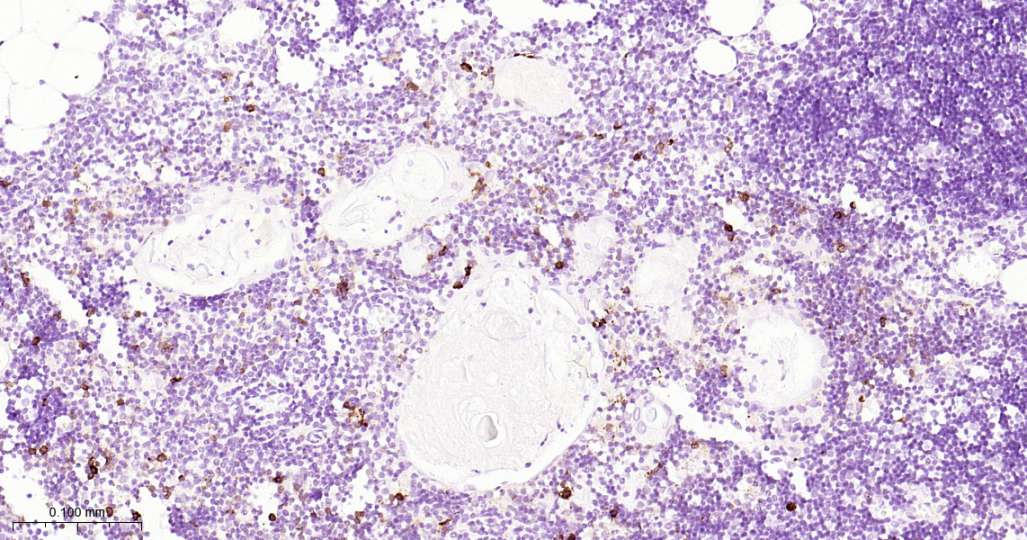

Immunohistochemical analysis of paraffin embedded Human thymus tissue slide using IHC0619H (Human CD134 Kit).

Immunohistochemical analysis of paraffin embedded Human lung cancer tissue slide using IHC0619H (Human CD134 Kit).

Immunohistochemical analysis of paraffin embedded Human tonsil tissue slide using IHC0619H (Human CD134 Kit).